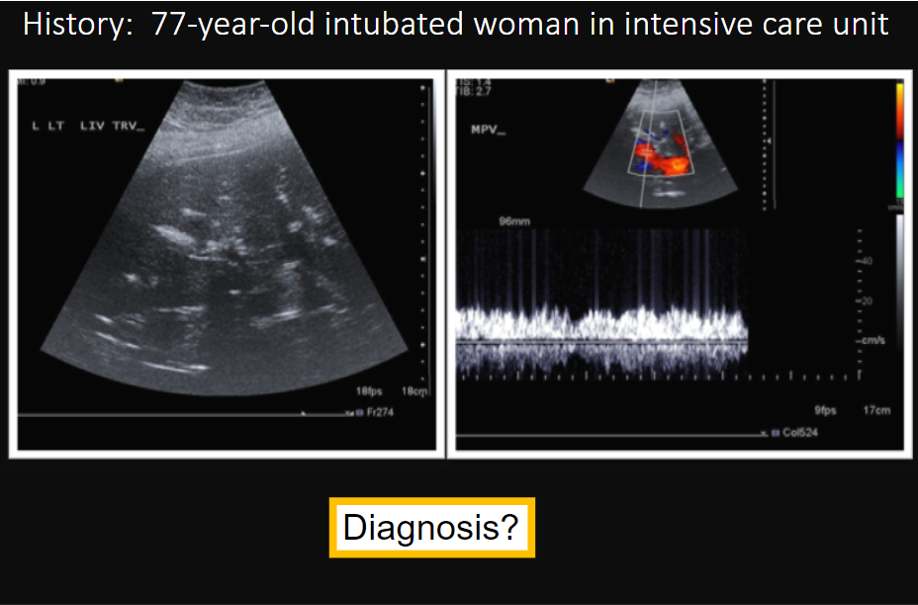

both of these are normal waveforms. Which is an upper and which is a lower extremity vein?